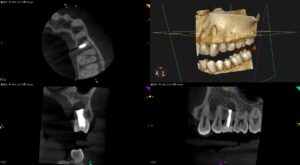

紹介患者さんの治療。 主訴は、 治療した歯の歯茎が腫れた。外科治療が必要だと言われ、紹介されたので来た である。 歯内療法学的検査(2025.4.11) #13 Cold N/A, Perc.(+), Palp.(+), … 続きを読む Re-RCTが奏功しなかった歯牙の外科治療〜#13 Intentional Replantationと1M recall